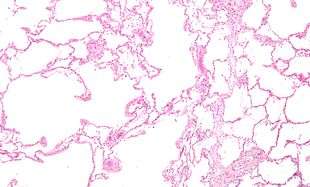

COPD is a type of obstructive lung disease in which chronic incompletely reversible poor airflow (airflow limitation) and inability to breathe out fully (air trapping) exist.[5] The poor airflow is the result of breakdown of lung tissue (known as emphysema) and small airways disease (known as obstructive bronchiolitis). The relative contributions of these two factors vary between people.[1] Severe destruction of small airways can lead to the formation of large air pockets—known as bullae—that replace lung tissue. This form of disease is called bullous emphysema.[52]

COPD develops as a significant and chronic inflammatory response to inhaled irritants.[1] Chronic bacterial infections may also add to this inflammatory state.[50] The inflammatory cells involved include neutrophil granulocytes and macrophages, two types of white blood cell. Those who smoke additionally have Tc1 lymphocyte involvement and some people with COPD have eosinophil involvement similar to that in asthma. Part of this cell response is brought on by inflammatory mediators such as chemotactic factors. Other processes involved with lung damage include oxidative stress produced by high concentrations of free radicals in tobacco smoke and released by inflammatory cells, and breakdown of the connective tissue of the lungs by proteases that are insufficiently inhibited by protease inhibitors. The destruction of the connective tissue of the lungs is what leads to emphysema, which then contributes to the poor airflow and, finally, poor absorption and release of respiratory gases.[1] General muscle wasting that often occurs in COPD may be partly due to inflammatory mediators released by the lungs into the blood.[1]

A severe case of bullous emphysema

Axial CT image of the lung of a person with end-stage bullous emphysema.

Very severe emphysema with lung cancer on the left (CT scan)